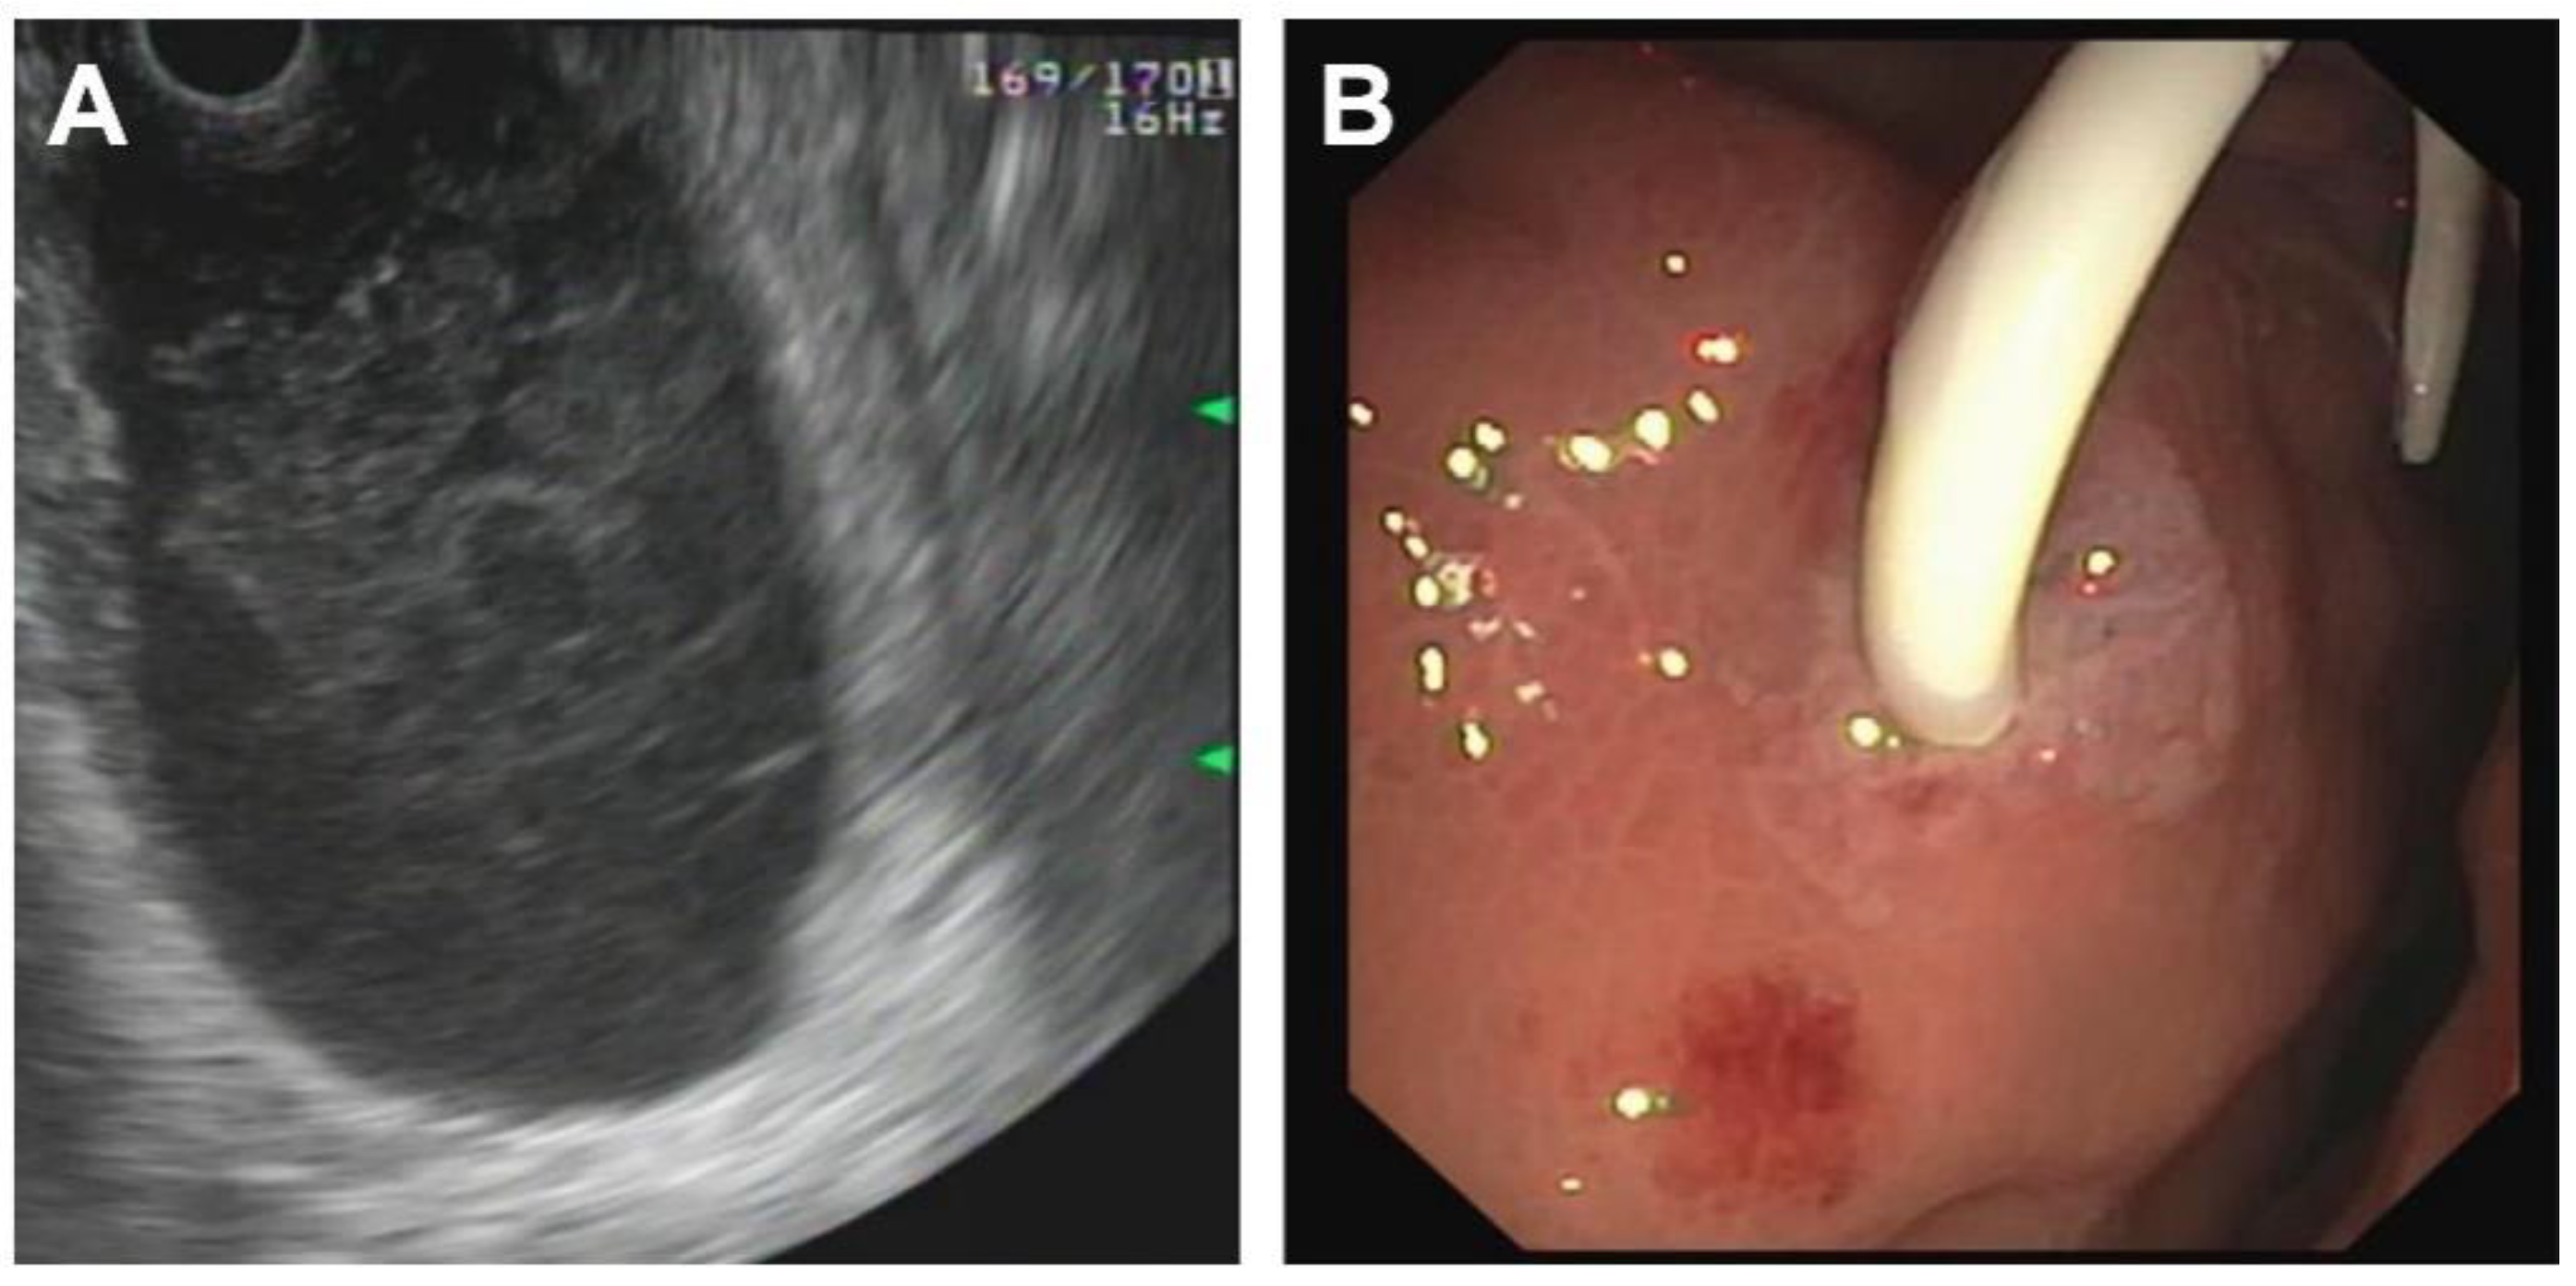

| Initial Management | Laparotomy, suture of the pancreatic head, distal pancreato-jejunostomy (Roux Y) | ERCP—complete dissection of the pancreas, Laparotomy, Jejunal repair, suture of the pancreatic head, distal pancreato-gastrostomy | ERCP—stenting of the ruptured pancreatic duct with 5 Ch pigtail drainage | ERCP unsuccessful, stenting of ruptured pancreatic duct not possible; chest drain (left side) |

| Management of complications | Anticoagulant therapy | - | Transgastric punction and drainage of pseudocyst with double-pig tail drain Ch 7, spontaneous dislocation of pig tail Antibiotic therapy Persistent fistula of the ruptured pancreatic duct, recurrent stenting (2 times), removal of stent after 5 months | Transgastric punction and drainage of pseudocyst with double-pig tail Ch 7, spontaneous dislocation of pig tail Antifungal therapy |